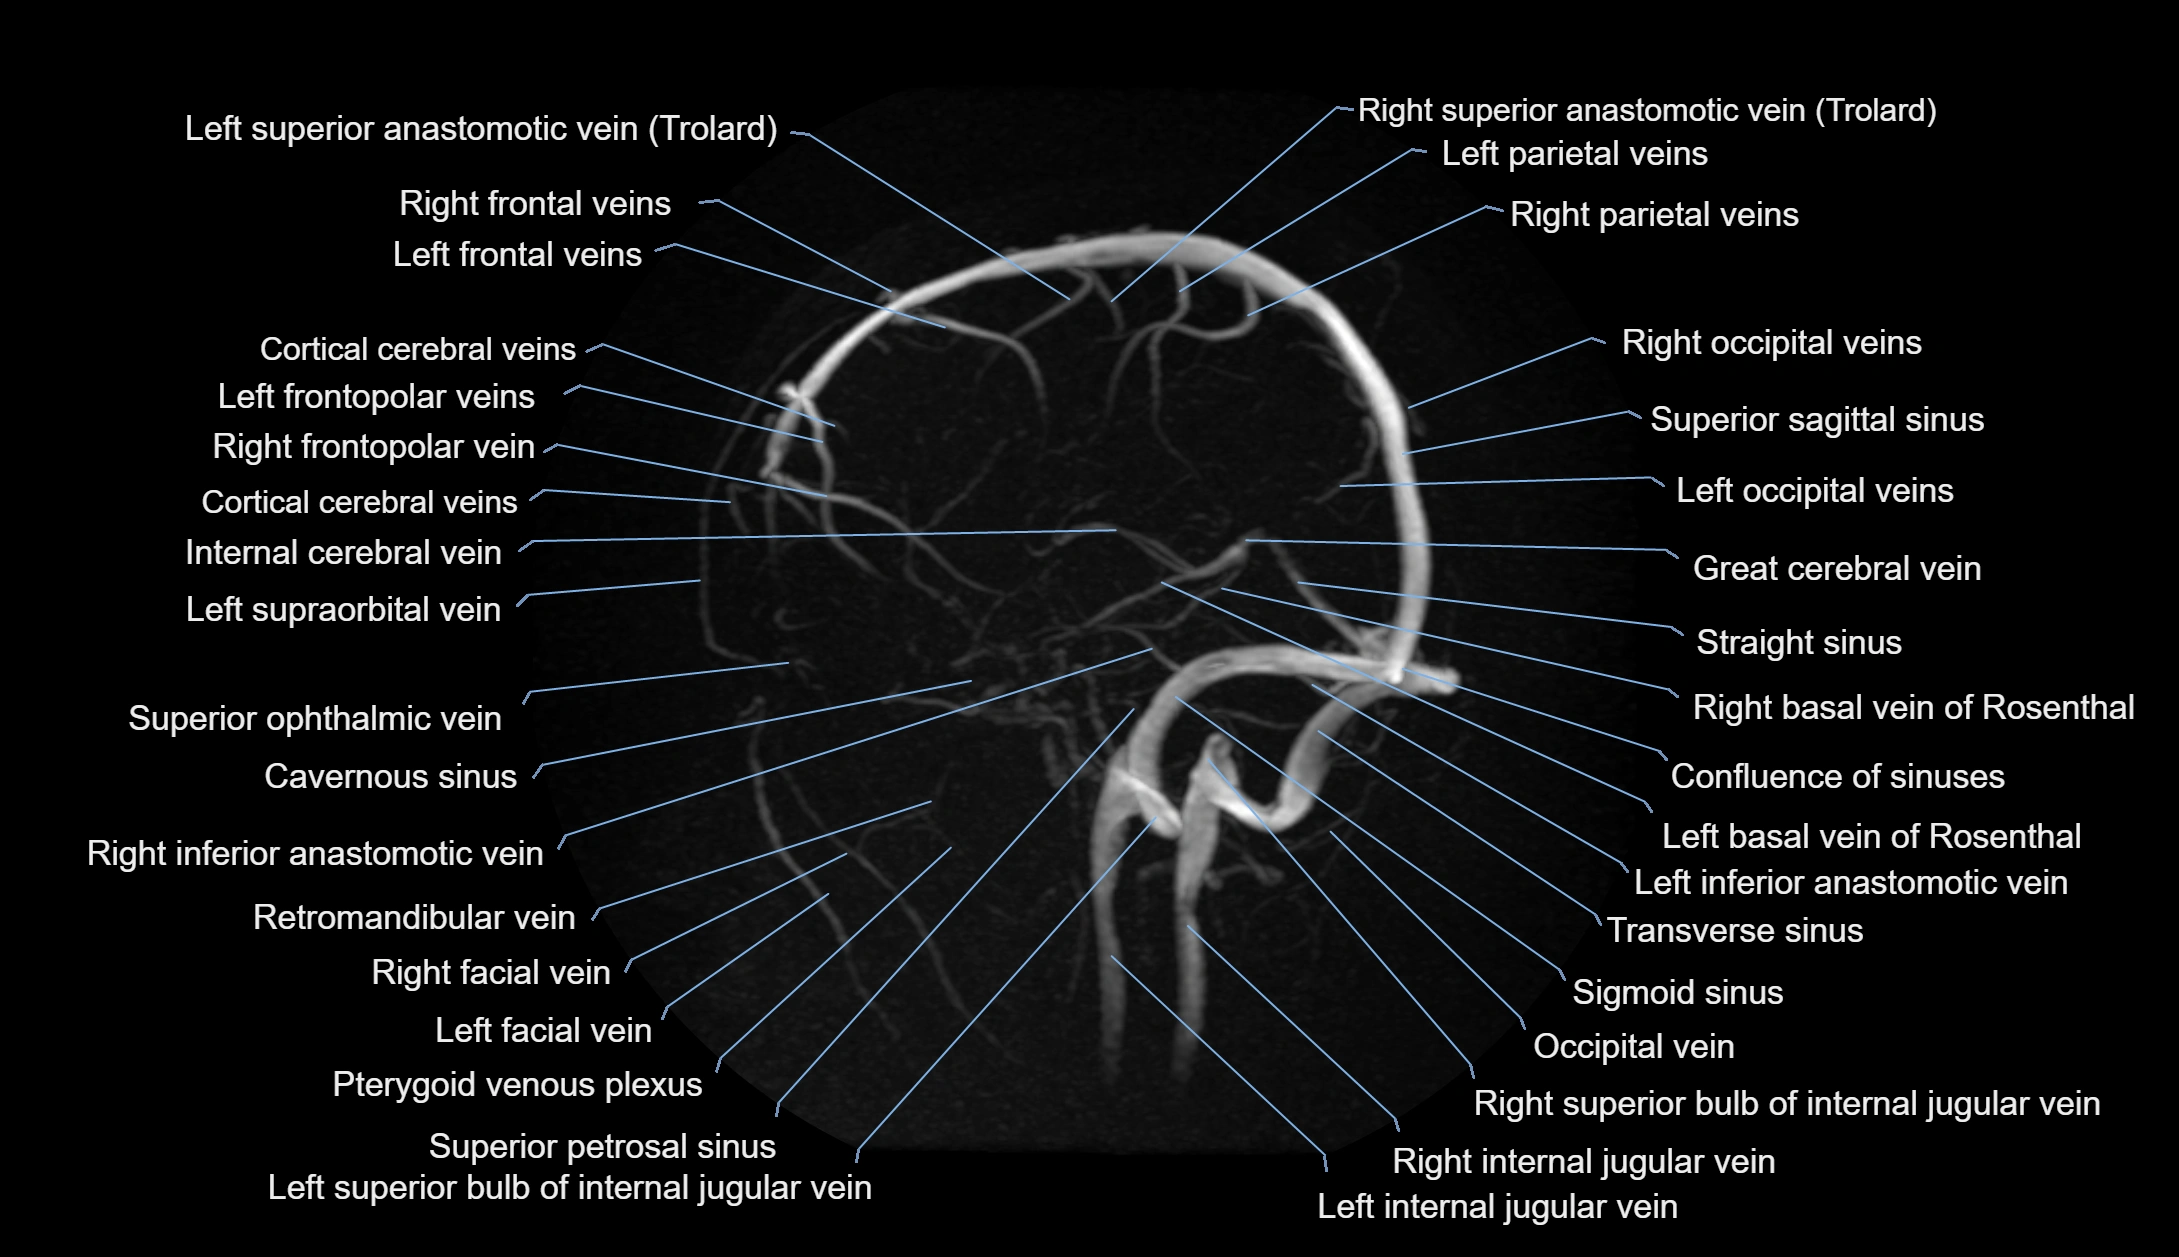

MR Venography (MRV):

• Time-of-flight (TOF) or contrast-enhanced MRV shows the angular vein as a bright enhancing venous channel

• Clearly demonstrates its continuity with the facial vein and superior ophthalmic vein

• MRV is highly useful in evaluating thrombosis, venous obstruction, or collateral venous drainage

MRI images